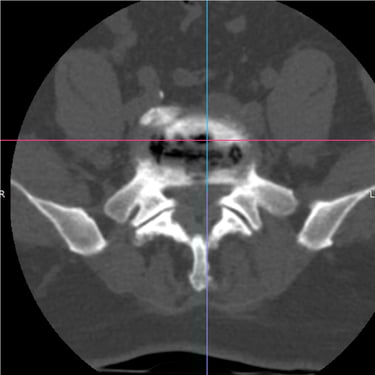

Columna lumbar inestable con listesis: tratamiento con artrodesis y tornillos transpediculares

La listesis lumbar ocurre cuando una vértebra se desplaza hacia adelante o hacia atrás respecto a la vértebra inferior, generando inestabilidad de la columna lumbar. Esta condición puede causar dolor lumbar crónico, compresión nerviosa, ciática, debilidad en las piernas o dificultad para caminar. Cuando el tratamiento conservador no es suficiente, la artrodesis lumbar con tornillos transpediculares es una alternativa quirúrgica eficaz. Este procedimiento permite fijar las vértebras afectadas mediante implantes que estabilizan la columna y favorecen la fusión ósea. Con técnicas modernas y abordajes mínimamente invasivos, se logra aliviar el dolor, mejorar la estabilidad vertebral y recuperar la función del paciente.